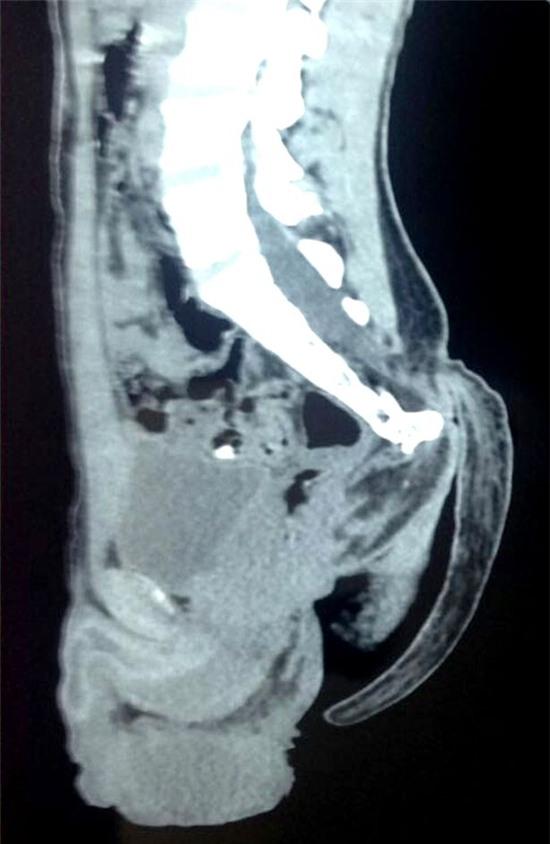

Các bác sĩ cho biết cái đuôi có thể đã phát triển từ trong bụng mẹ như kết quả của một dị dạng ống thần kinh. Tuy nhiên, cái đuôi chỉ mọc ra sau khi cậu lớn lên.

Một nhóm các nhà phẫu thuật thần kinh tại Bệnh viện Chuyên môn đã gỡ bỏ thành công cái đuôi ra khỏi lưng của thanh niên, và dường như đây là cái đuôi dài nhất từng được ghi nhận cho đến nay.

Người đứng đầu khoa phẫu thuật thần kinh, bác sĩ Pramod Giri cho biết: "Trường hợp này là rất hiếm. Chúng ta cần gọi đến các tạp chí y khoa để công nhận chính thức đây là cái đuôi dài nhất từng được ghi nhận cho đến nay."

Theo các bác sĩ, cái đuôi là kết quả của một dị dạng ống thần kinh